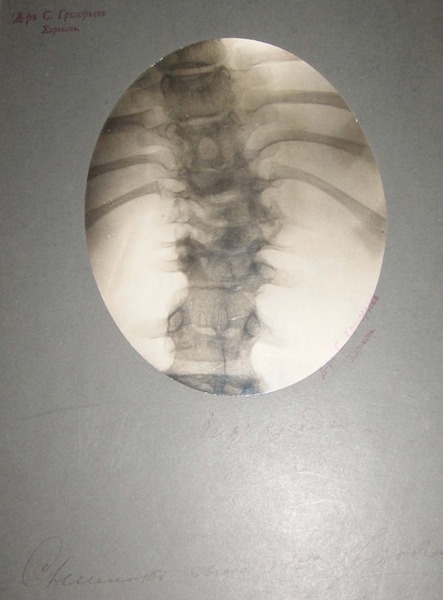

- Рентгенівський знімок лікаря С.П. Григор’єва, 1916